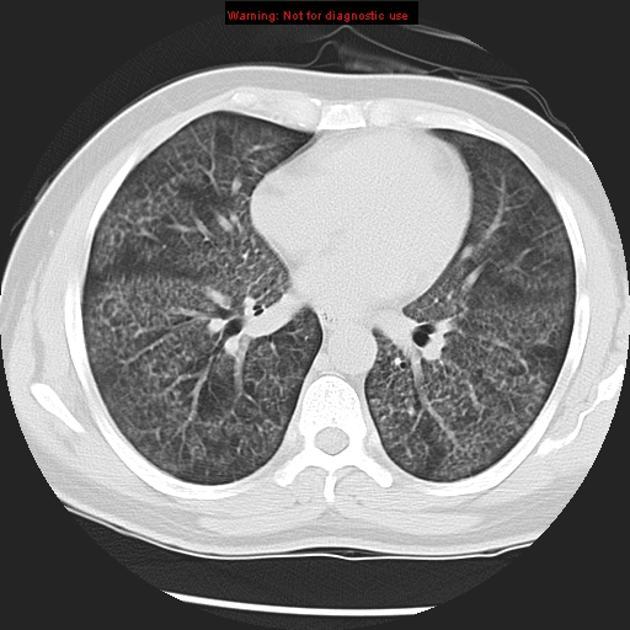

PACIENTE 35 ANOS, SEXO MASCULINO, DISPNÉIA HÁ 4 DIAS.

opacidades em vidro fosco difusas associadas a espessamento de septos interlobulares (crazy paving)

PROTEINOSE ALVEOLAR